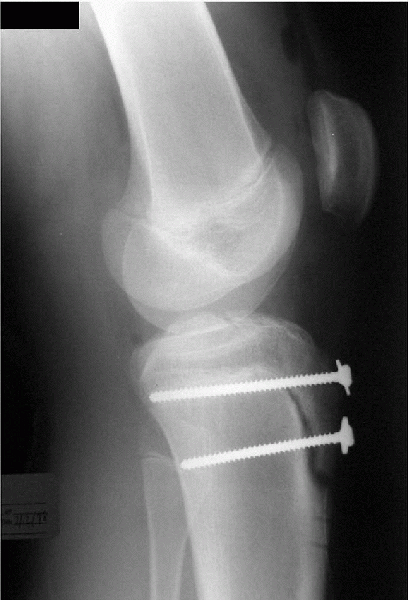

The fracture is graded by degree of separation from minimal displacement to intra-articular extension and gross displacement (Fig. 5-10).

Displacement of more than 5 mm is treated with open reduction internal fixation with two screws (Fig. 5-11, Algorithm 5-8).

Figure 5-10 A:

Classification of tibial tubercle fractures. Type I has minimal separation. Type II requires fixation, and type III displays intra-articular extension. Type IV is a SH-I fracture of the entire tibial physis. Type V is a combination of types III and IV. B: A type III fracture is shown. |

Figure 5-11

Repair of the displaced tibial tubercle fracture. The screws can cause pain with kneeling and are frequently removed. Problems with growth arrest leading to knee recurvatum have rarely been reported. |